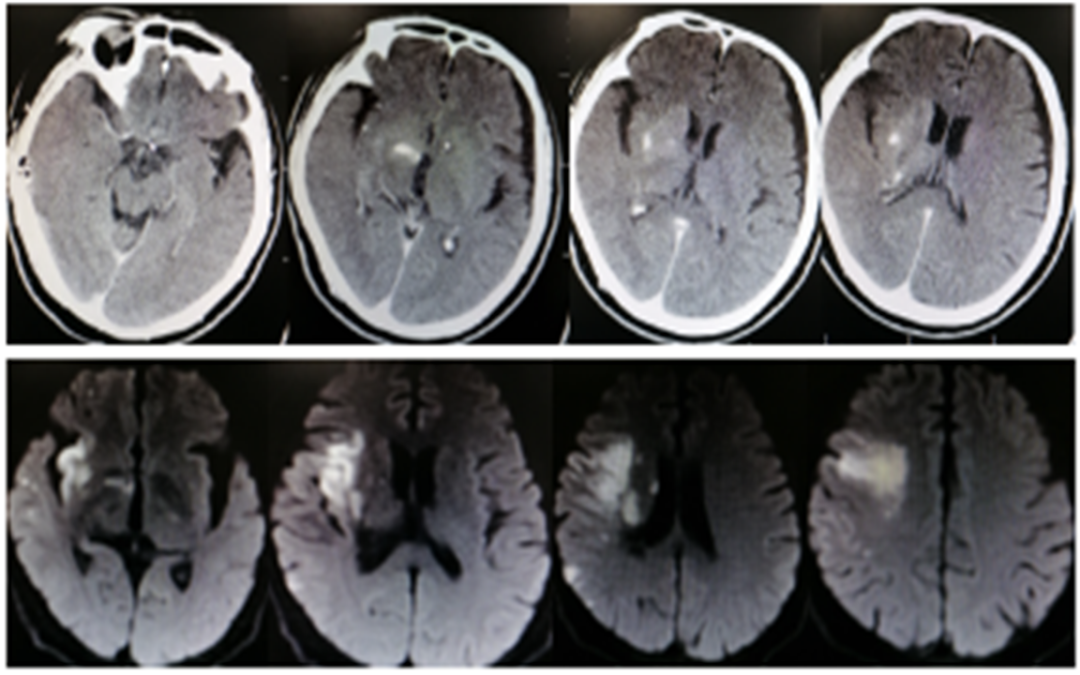

结论:颅脑CT提示左侧基底节、放射冠区腔隙样软化灶。颅脑DWI提示双侧小脑、桥脑、中脑、双侧海马、双侧枕叶、右侧丘脑及右侧胼胝体多发急性脑梗塞。颅脑MRA提示基底动脉及双侧大脑后动脉未见显示;右侧大脑中动脉中-重度狭窄;脑动脉硬化。初步诊断为急性后循环脑梗死,基底动脉闭塞。

• 左侧椎动脉造影见基底动脉起始处闭塞。

• 微导管造影,见基底动脉尖及左侧大脑后动脉显影不良,考虑栓塞。

• 基底动脉近端打开支架,支架形态尚可,局部发白,左侧大脑前动脉P1段栓塞。

• 支架取栓取出一小块栓子,造影见基底动脉起始处重度狭窄。

• 狭窄处予球囊扩张成形,球扩后造影见基底动脉狭窄有所改善。

• 微导管送至左侧大脑后动脉P2段,造影确认真腔后,释放支架,并支架取栓1次。

• 血栓成功取出,基底动脉侧位造影,左侧大脑后动脉再通。

• 正位造影,左侧大脑后动脉再通,无血栓逃逸,基底动脉狭窄改善,未回缩,前向血流正常,观察后结束手术。

• 患者术后转入重症医学科,症状一直未有改善,昏迷状,术后第5天家属放弃治疗自动出院。